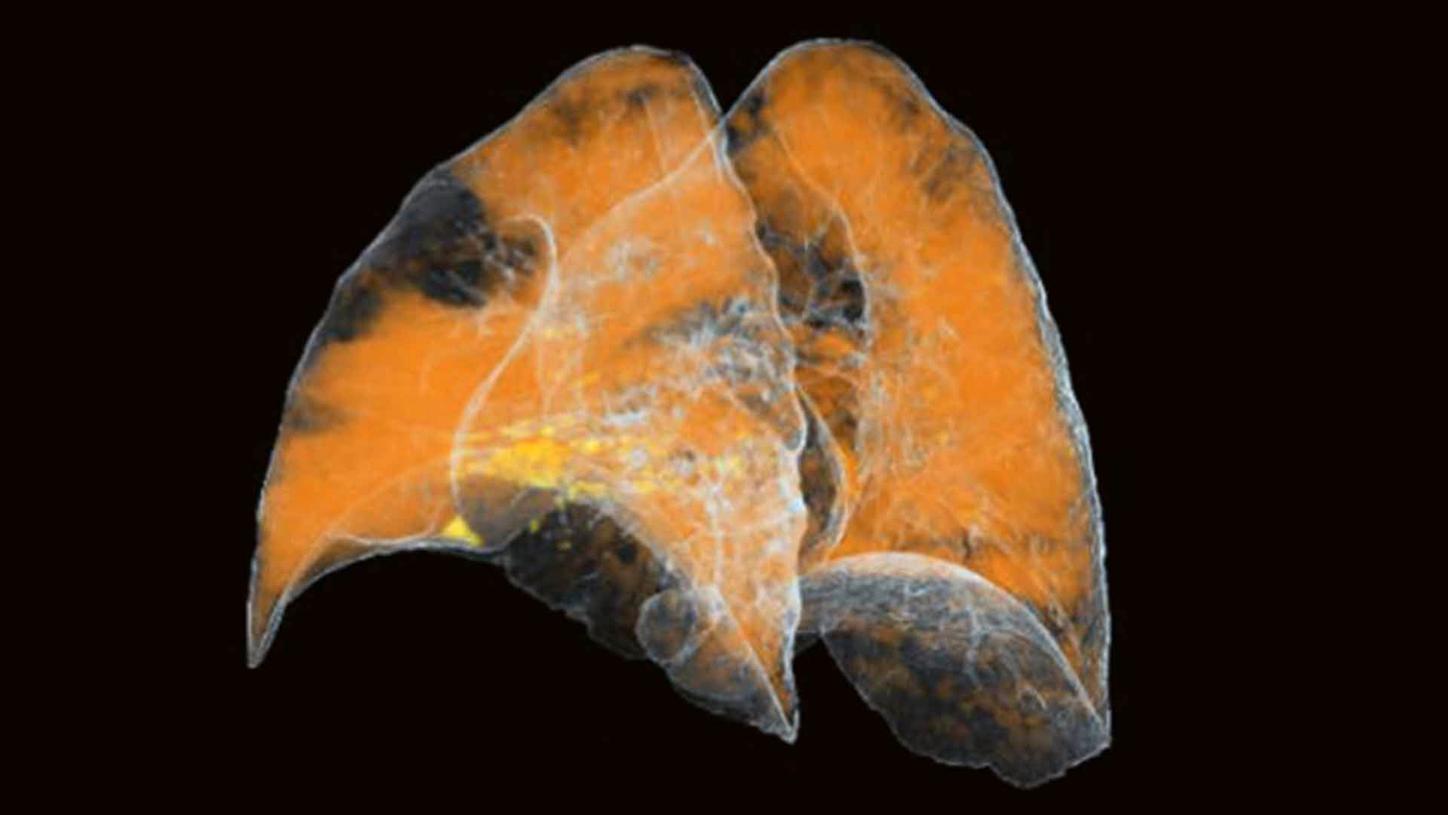

Application Training for Computed TomographyCourse overview - explore our offerings

These courses are offered as classroom training in our Training Centers or as as virtual classroom training independently where you are located. Theoretical principles of imaging are supplemented by a wide range of practical exercises, giving you the opportunity to gain skills for day-to-day clinical work. In our virtual courses we impact practical knowledge in clear, manageable units and focus on retaining the interactive approach that you are familiar with from our face-to-face training. Learn in the virtual work space and benefit from innovative digital methods.